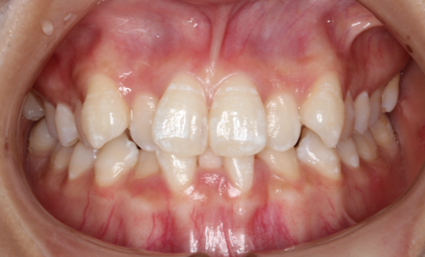

「矯正」と聞くと、多くの方が「表側矯正(唇側矯正)」を思い浮かべるのではないでしょうか。表側矯正では、矯正装置を歯の表側(唇側)に装着します。治療中に装置を取り外すことはできません。これにより、確実に歯を矯正することができます。

従来の表側矯正では、金属製のワイヤーや装置が目立ってしまうことがありました。口を開けると、矯正装置がはっきりと見えるため、見た目を気にされる方も少なくありません。しかし、最近では白いパーツを用いた装置が登場し、従来の金属製の装置に比べて目立たないよう工夫されています。このような改良により、審美性を保ちながら治療を進めることが可能です。

表側矯正は、他の矯正方法と比較して費用が比較的安価であることも大きな魅力です。予算に制限がある場合でも、手軽に始められる治療法として人気があります。また、軽度から重度の歯並びまで、幅広い症例に対応できるのも特徴の一つです。

また、当院では表側矯正ではなく、装置を歯の裏側に装着する「裏側矯正(舌側矯正)」も可能です。表側矯正よりもさらに審美性の高い治療が可能です。ご興味のある方はぜひご相談ください。